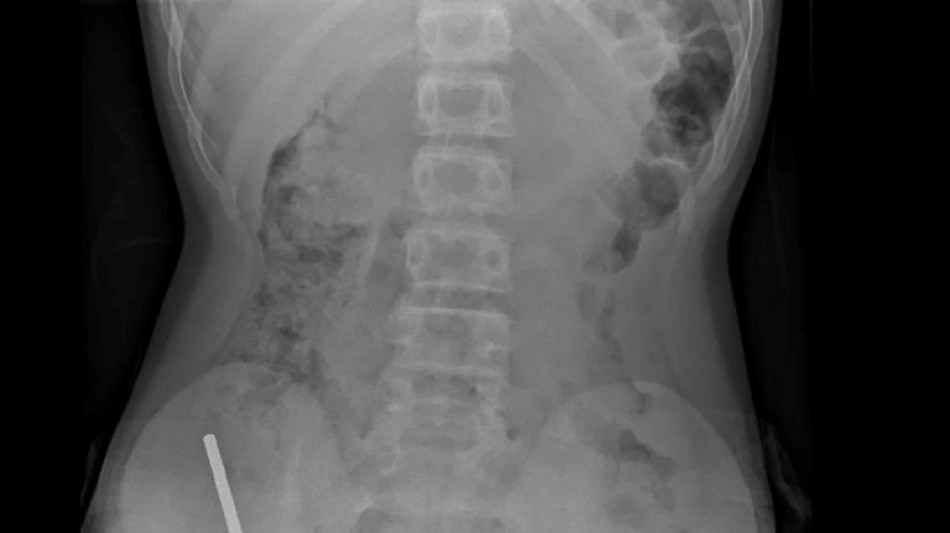

Nouvelle-Zélande: un adolescent opéré après avoir ingéré près de 100 aimants achetés sur Temu / Photo: Handout - NEW ZEALAND MEDICAL JOURNAL (NZMDJ)/AFP

En Nouvelle-Zélande, un adolescent de 13 ans s'est vu retirer plusieurs parties nécrosées de ses intestins après avoir avalé près d'une centaine d'aimants achetés en ligne sur le site Temu, a rapporté vendredi une revue médicale.

Après avoir souffert de douleurs abdominales pendant quatre jours, l'adolescent a été transporté à l'hôpital de Tauranga, sur l'île du Nord.

"Il avoué avoir ingéré entre 80 et 100 aimants puissants au néodyme, de 5x2mm environ, une semaine plus tôt", indique un rapport des médecins de l'hôpital de cet hôpital, publié dans le New Zealand Medical Journal (NZMJ).

Les médecins ont déclaré que la pression exercée par les aimants avait provoqué une nécrose dans quatre zones de l'intestin grêle et du gros intestin du garçon.

Il a été opéré afin que l'on lui retire les aimants et les tissus nécrosés, et il a pu rentrer chez lui après huit jours à l'hôpital.